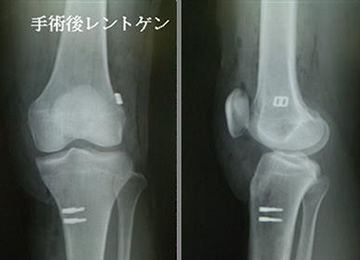

自分の組織を用いて再建する(自家腱移植)のがベストな方法とされています。当院で行っている膝屈筋腱(ハムストリングス)を用いた関節鏡視下膝前十字靱帯再建術は、切開は最小限で大きな合併症がなく、術後の成績も安定しているため、有効な治療方法として確立されています。 手術は膝関節を構成する大腿骨と脛骨の最適部位に関節鏡を用いて細いトンネルを作製し、そこに採取加工した腱を貫いて上端と下端を金具で固定することで膝の安定性を得ることを目的とし、全身麻酔+硬膜外持続麻酔下で行います。尚、本院では遺残靱帯(レムナント)が残存している患者様に対しては再生医療の観点※からレムナントを切除せずレムナントを利用し一重束前十字靱帯再建術(レムナント温存法)を、また女性で膝が柔らかい患者様(反張膝の患者様)などには二重束前十字靱帯再建術を、また二度目の受傷の患者様などには膝蓋腱を用いて一重束前十字靱帯再建術(BTB法)をおこなっています。また、縫合可能な半月板損傷がある患者様に対しては全例半月板縫合を行います。(Biomet MaxFire™ を利用し、関節内だけの操作で縫合します。)手術時間はレムナント温存法で行った時は約1時間から1時間半です。

再建靱帯を固定するボタンとステープル(チタン製)